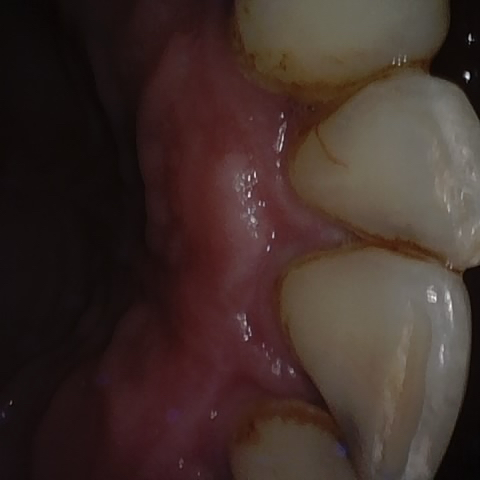

Annotated as "Good"